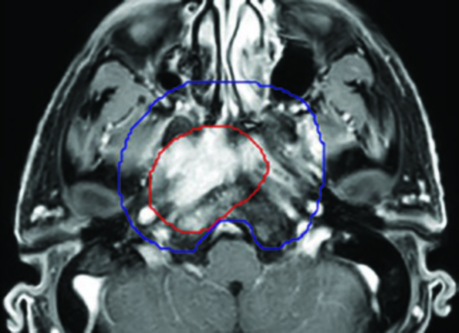

Caso 2: T4N2 EBV positivo

Paciente con enfermedad localmente avanzada, extensión intracraneal a través del foramen oval y seno cavernoso ipsilateral, adenopatías bilaterales en niveles II-V. El GTV70 incluyó el tumor primario con toda su extensión intracraneal visible en RM T1 con gadolinio, así como el conglomerado ganglionar necrótico. El CTV70 se expandió 5 mm en la mayoría de las direcciones, reduciéndose a 0 mm en la interfaz con el lóbulo temporal. El CTV subclínico requirió la inclusión del seno esfenoidal completo, el clivus completo, la cavidad de Meckel bilateral y todos los niveles cervicales bilaterales hasta la grasa posterior a la clavícula en el nivel V.

Ambos casos fueron tratados con quimiorradioterapia concurrente con cisplatino, esquema SIB en 33 fracciones (70 Gy al PTV70, 56 Gy al PTV56), con verificación mediante CBCT diario.